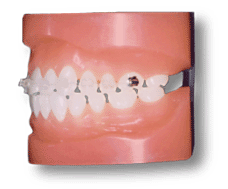

メタルブラケット

何といっても一番しっかりしている。装置費用も割安。審美的には△。